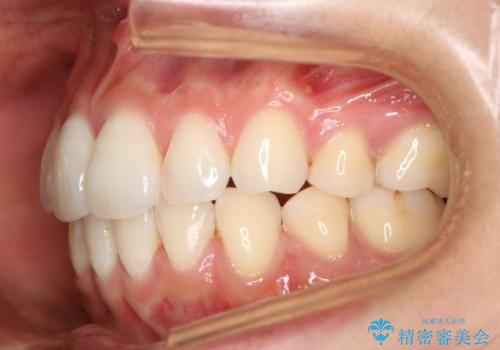

- 治療計画

- 2年8ヶ月